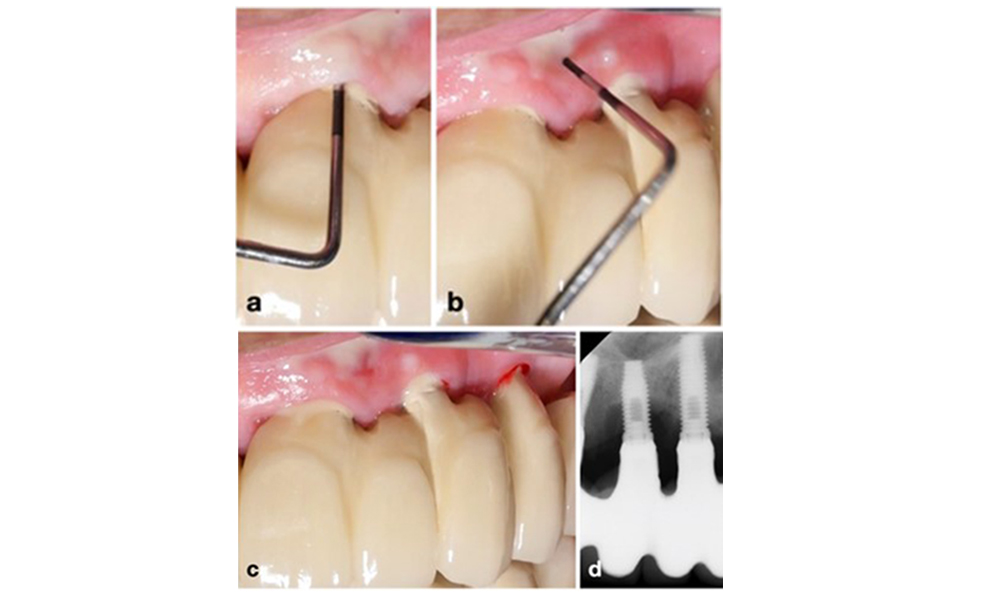

A Mnemonic Approach to Radiographic Precision

To achieve consistent and comparable radiographs over time without overlapping implant-threads, a simple mnemonic rule can be followed: “right blur, raise beam & left blur, lower beam – RBRB/LBLB” (see figure 3 adapted from Schropp et al. 2012).

For optimal intraoral radiographs of dental implants, follow this mnemonic rule: If the right side of the implant appears blurry on the peri-apical x-ray, raise the beam (i.e., directed more towards the ceiling) (a); if the left side appears blurry, lower the beam (i.e., directed more towards the floor) (b). This rule applies regardless of implant position in the upper or lower jaw. Example: Blurry threads on implants at positions 14 and 16, mostly at their right side, (c) were corrected by raising the beam by about 15 degree, resulting in a clear image showing bone-to-implant contact (d).

Figure 3. For optimal intraoral radiographs of dental implants, follow this mnemonic rule: If the right side of the implant appears blurry on the peri-apical x-ray, raise the beam (i.e., directed more towards the ceiling) (a); if the left side appears blurry, lower the beam (i.e., directed more towards the floor) (b). This rule applies regardless of implant position in the upper or lower jaw. Example: Blurry threads on implants at positions 14 and 16, mostly at their right side, (c) were corrected by raising the beam by about 15 degree, resulting in a clear image showing bone-to-implant contact (d).